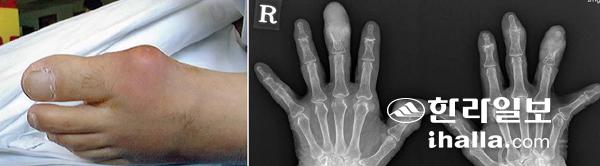

왼발 중족지 관절에 생긴 급성통풍관절염(사진 왼쪽). 특징적으로 이환된 관절이 붓고, 붉어지는 염증소견을 보인다. 만성 결정성 통풍환자의 손(사진 오른쪽). 단순 방사선검사 소견으로 손가락 원위지관절로 통풍결절이 침범돼 특징직인 골미란(뼈가 녹아나는 현상)이 관찰된다.